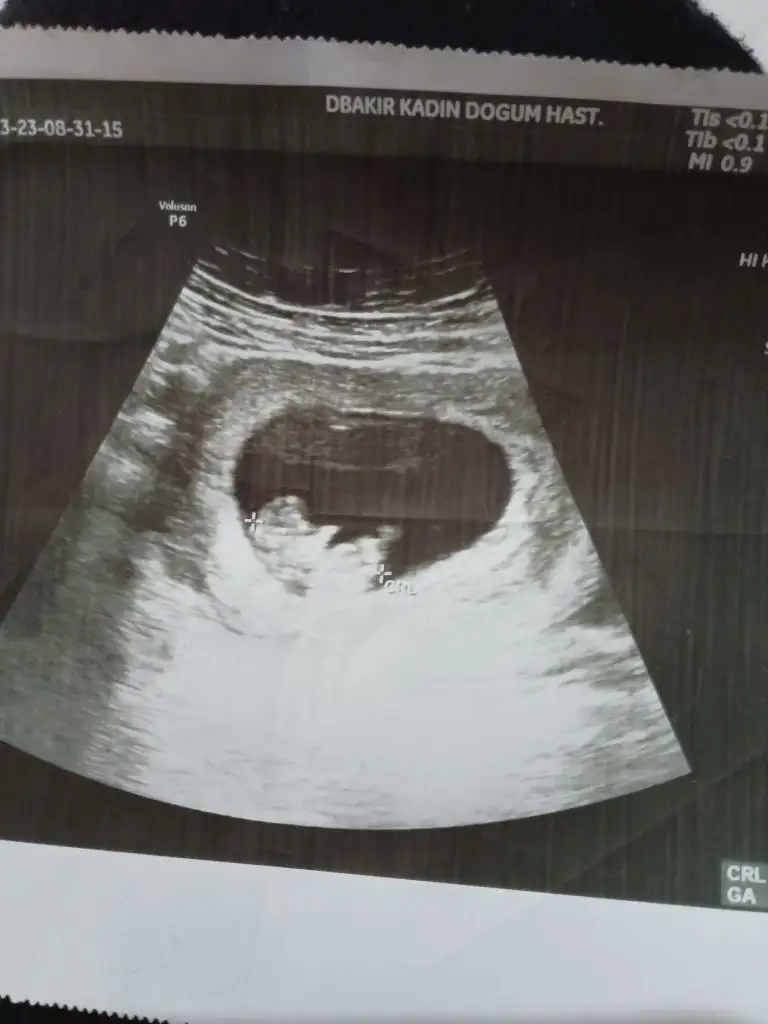

Oğlumun kardeşinin cinsiyetini tahmin etmek isteyen var mı hanımlar?Nub ve ramzi teorisinden anlayanlar lütfen bana da tahminde bulunabilirmisiniz Şimdiden çok teşekkürler

• 7D0C2DF2-224A-4A4E-800F-301F7160D4C0.webp

42,6 KB · Görüntüleme: 240